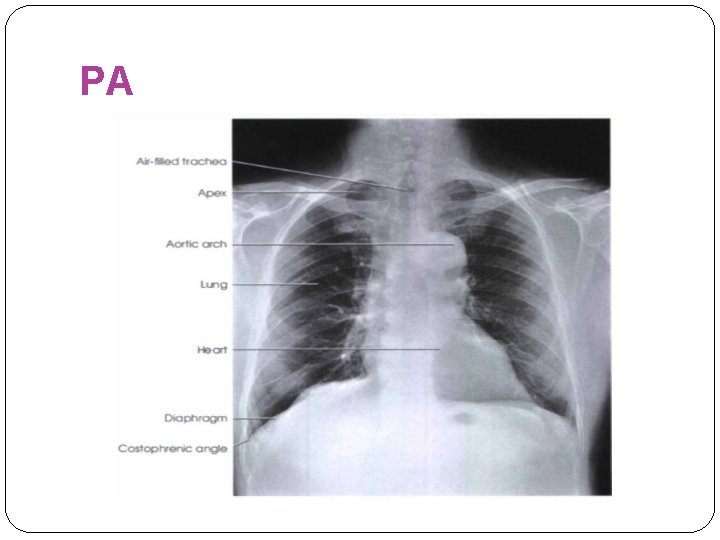

PA